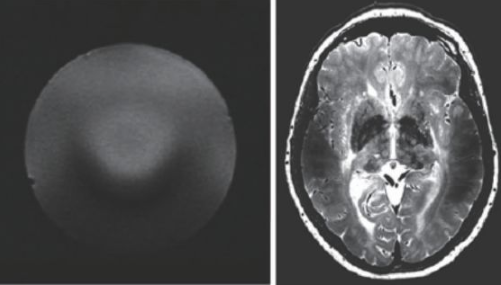

超高場MRI的射頻場設計也是一個較為困難的問題。由于射頻頻率超過了300 MHz,介電常數(shù)引起的問題非常突出。圖13 是一個在7 T 下的成像結果,可以看到在圖像內(nèi)部的信號非常不均勻,由于射頻波長的極度縮短,組織的介電常數(shù)對射頻場的分布有極大的影響,這也是目前超高場MRI 需要解決的重要問題之一。目前的9.4 T以上的MRI設備還難以獲得人體體部掃描的良好圖像,其主要應用還是做頭部的掃描。

圖13 超高場下的射頻場不均勻性